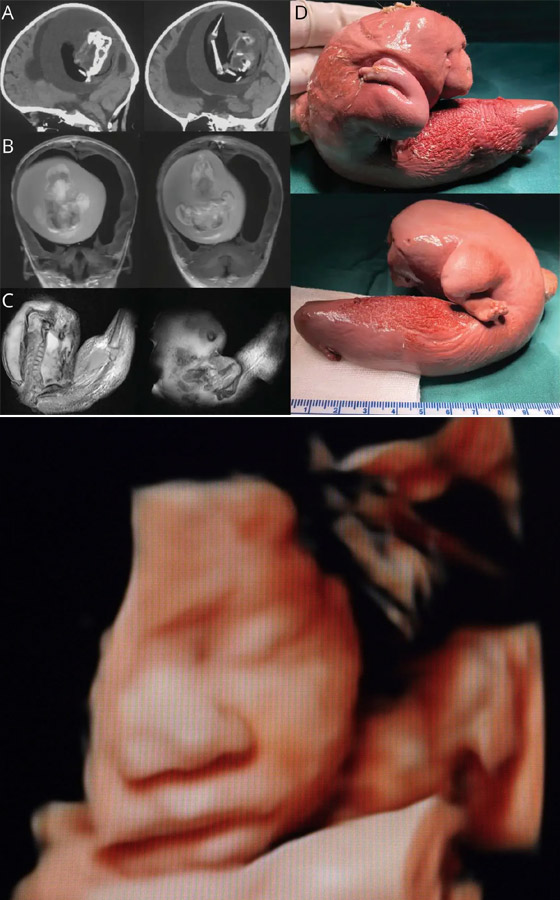

2. إزالة جنين من دماغ طفل عمره عام واحد

في حالة نادرة للغاية، قام الأطباء بإزالة جنين جراحيا من دماغ طفل يبلغ من العمر عاما واحدا. كان الجنين هو التوأم المتطابق للطفل، فقد جاء من نفس البويضة المخصبة وشاركه أيضا نفس المشيمة، ولكنه تطور في كيس منفصل. خلال فترة الحمل، كان أحد الجنينين مغلفا بالآخر، لكن بقاياه بقيت في جمجمة الطفل المتبقي حتى بعد الولادة، مما تسبب في تضخم الرأس وتأخر نمو المهارات الحركية.